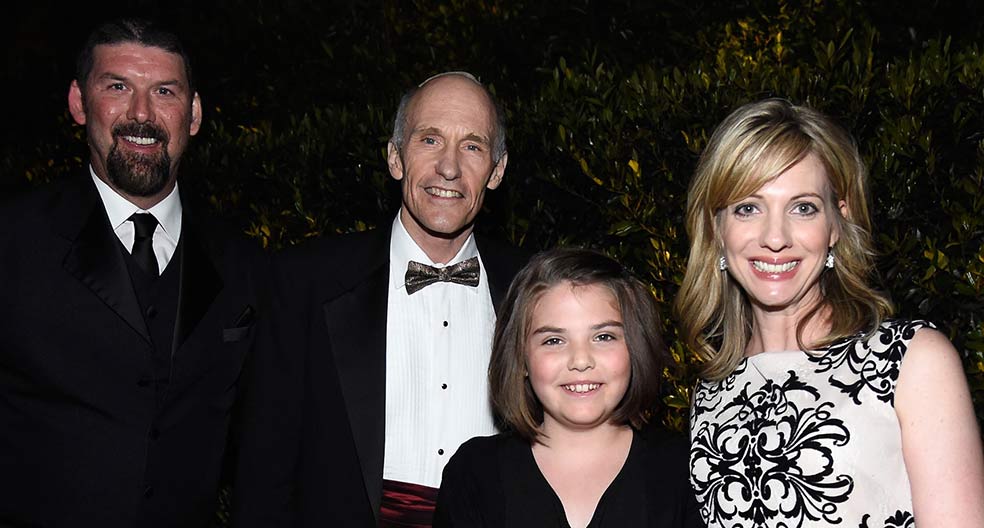

Aquella intervención se convirtió en un hito en el tratamiento del cáncer. Entonces la esperanza de los científicos era que la terapia pudiera, en el futuro, sustituir al trasplante de médula ósea, aunque en ese momento solo era una alternativa válida para «personas que no tienen otras opciones curativas», explica el doctor Stephen Grupp. Diez años después, se acaban de presentar los resultados de ese trabajo que confirma que los dos primeros pacientes tratados continúan sanos. Según un artículo de la revista Nature, no hay rastro de células de leucemia en ninguno de los dos y, además, como señala el doctor Carl June, el médico que trató a Emma y uno de los pioneros en utilizar esta estrategia, las células T siguen estando en los pacientes y tienen la capacidad de matar a las células cancerosas.

Sirviéndose de una variante neutralizada del virus del sida, un grupo de científicos liderados por el doctor Carl June (en la foto, junto a Emma) lograron reprogramar el sistema inmune de varios pacientes con leucemia linfoblástica severa para combatir el cáncer.